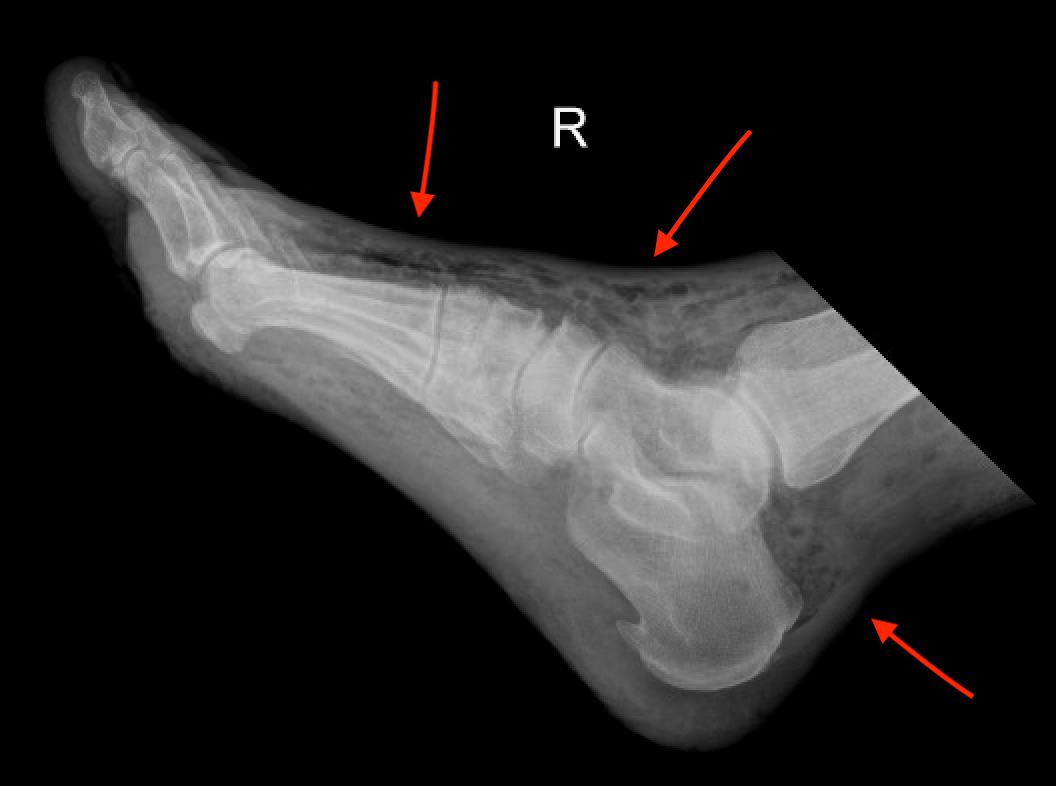

Answer: Necrotizing Fasciitis

Subcutaneous air in surrounding soft tissue

necrotizing fasciitis xray.